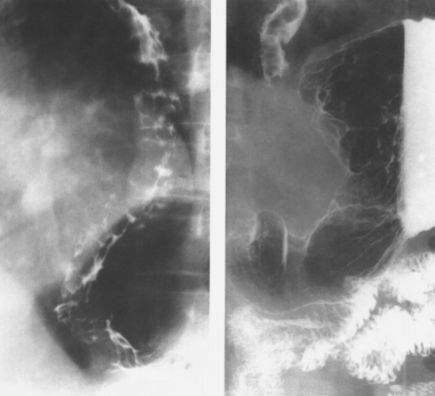

食管静脉曲张:蚯蚓样、串珠状。

食管重度静脉曲张

食管静脉曲张:食管黏膜呈现蚯蚓状

这是食管静脉曲张伴胃底静脉曲张的图像